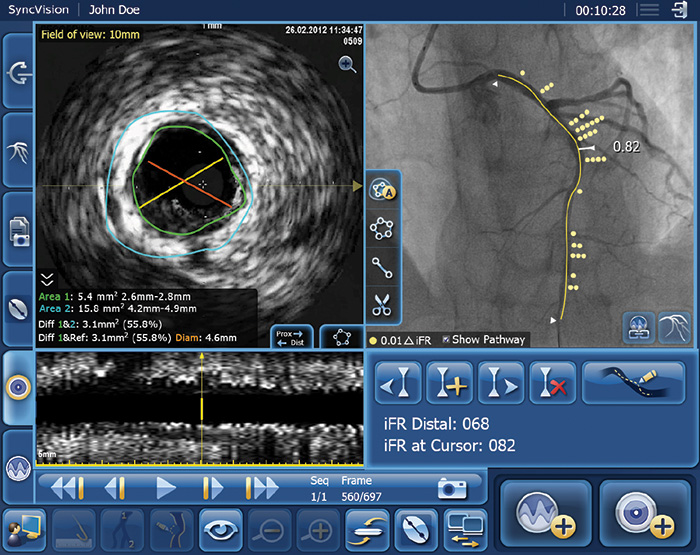

The DEFINE GPS (Distal Evaluation of Functional performance with Intravascular sensors to assess the Narrowing Effect: Guided Physiologic Stenting) study will evaluate the use of iFR measurements in combination with Philips Image Guided Co-Registration System – SyncVision – to enhance PCI guidance and provide superior treatment outcomes. DEFINE GPS is a follow-up to the DEFINE PCI study [1] – a one-year trial sponsored by Philips that evaluated the potential of treating residual ischemia in order to improve clinical outcomes for coronary stent patients.

PCI is an image-guided, minimally-invasive treatment to open a coronary artery blockage (stenosis) that is causing a reduced blood flow (ischemia) to heart tissue. Under the current standard of care, clinicians navigate a balloon catheter and coronary stent to the treatment area using interventional X-ray guidance (a coronary angiogram). In the DEFINE GPS study, an iFR pullback measurement, which uses pressure wires to map the physiological profile of disease distribution along the length of the affected vessel, will be overlaid on the angiogram to provide more precise information on where to treat within the vessel. The study will also use iFR to measure if the treatment succeeds in restoring sufficient blood flow to prevent ischemia or if further treatment is warranted.

Philips Image Guided Co-Registration System – SyncVision – is part of the company’s unique portfolio of systems, smart devices, software and services available on its Image Guided Therapy System – Azurion. In addition to advanced imaging systems, the portfolio includes coronary imaging catheters, coronary atherectomy and coronary crossing devices, specialty balloons, flow wires, and pressure wires such as Philips’ new OmniWire – a unique solid-core pressure wire that enhances the ability to maneuver the wire in the patient’s circulatory system.